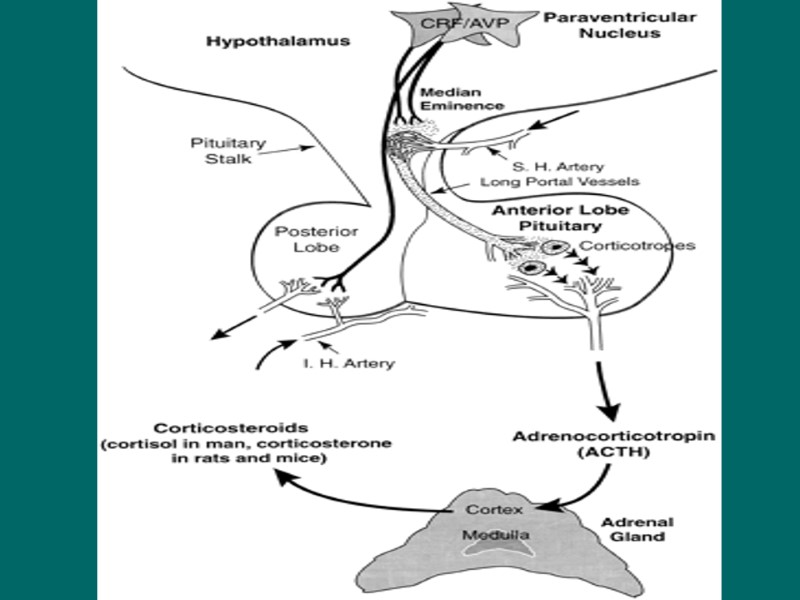

Гипоталамо-гипофизарно нейросекреторный комплекс – высший нейроэндокринный трансмиттер организма, координирующий эндокринную регуляцию метаболизма с работой ВНС и интегральными эмоционально-поведенческими реакциями лимбической системы. Состоит из: - Гипоталамус; - Нейрогипофиз; - Аденогипофиз

Группы биорегуляторов, продуцируемых гипоталамусом Либерины и рилизинг-факторы (тиролиберин, кортиколиберин …); Статины и ингибитинг-факторы (соматостатин, пролактостатин? ...); Нонапептиды (вазопрессин и окситоцин); Моноамины (дофамин, серотонин, гистамин …); Эндогенные опиоиды; Другие нейропептиды

Гипофиз – орган, обеспечивающий процессы метаболизма и репродукции организма. - Аденогипофиз; - Нейрогипофиз

Формы участия вазопрессина при стрессе Экономия водных и волемических ресурсов организма за счёт реабсорбции воды без задержки натрия; Сильный вазоконстрикторный агент; Гепатотропный гормон – активатор обменных процессов; Стимулирование процессов памяти

Аденогипофизарные клетки Соматотропы – 40 – 50 % (СТГ); Лактотропы – 20 % (Пролактин); Тиротропы – 6 % (ТТГ); Гонадотропы – 3 – 4 % (ЛГ и ФСГ); Хромофобы – 20 % ??? Кортиколипотропы – 15 – 20 % (ПОМК – пропиомеланокортин → МСГ, АКТГ, α- и β- эндорфины, N-концевой гликопептид…)

АКТГ – как гормон стресса Инсулиноподобное и стимулирующее СТГ действие; Липолитический эффект; ↑ - потребление АК в мышцах и внутриклеточный транспорт глюкозы; ↓ - обранование мочевины и распад ГКС в печени; Поведенческие реакции; Противовирусный эффект